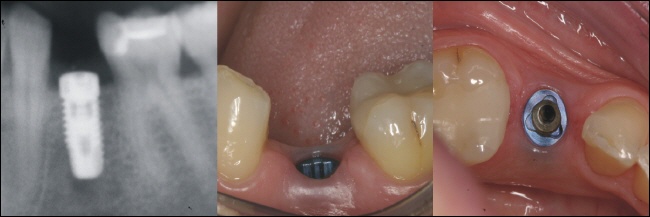

Ein Implantat besteht in der Regel aus reinem Titan und stellt ein der Zahnmedizin den künstlichen Ersatz einer natürlichen Zahnwurzel dar.

Auf das schraubenförmige Implantat wird mit einer Schraube ein Aufbau (Pfosten) geschraubt. Dieser bietet die Basis für den Zahnersatz. Auf den Aufbau wird beispielsweise eine Krone, eine Brücke oder auch andere Halteelemente, wie zum Beispiel ein Teleskop, aufzementiert.

1. Das Implantat

Das Implantat ist der künstliche Ersatz der natürlichen Zahnwurzel

2. Der Aufbau

Auf dieses Implantat wird ein so genannter Aufbau aufgeschraubt. Dieser bekommt seinen Halt über eine spezielle Innenverbindung, oder in seltenen Fällen über eine Außenverbindung. Diese Verbindung bietet den Rotationsschutz des Aufbaus und der Krone.

3. Die Suprakonstruktion

Die Suprakonstruktion (Krone) ist letztlich das einzige, was später noch im Mund zu sehen ist. Sie wird auf den Aufbau festzementiert oder aber mit dem Aufbau verschraubt.